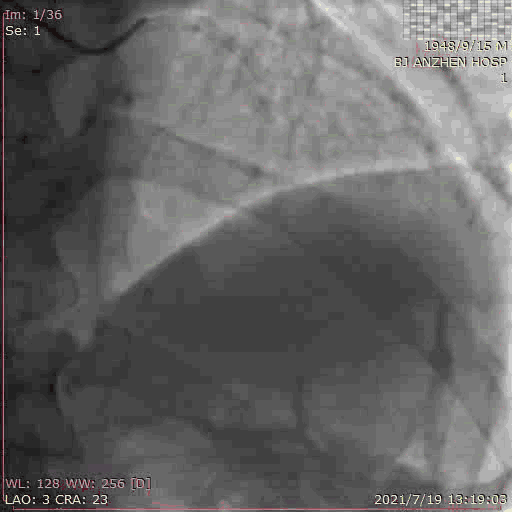

TAVR过程:患者局麻后,植入临时起搏器,穿右股动脉送入23mm球囊预扩张病变,左、右冠状动脉未受明显影响,决定直接植入爱德华SAPIEN 3 26mm 球扩式瓣膜,选择标准位进行释放。

释放后主动脉窦造影提示瓣膜膨胀良好,主动脉瓣周少量反流。术后即刻TTE提示跨瓣最高流速109cm/s,平均跨瓣压差3mmHg。主动脉瓣瓣口面积2.72cm²。